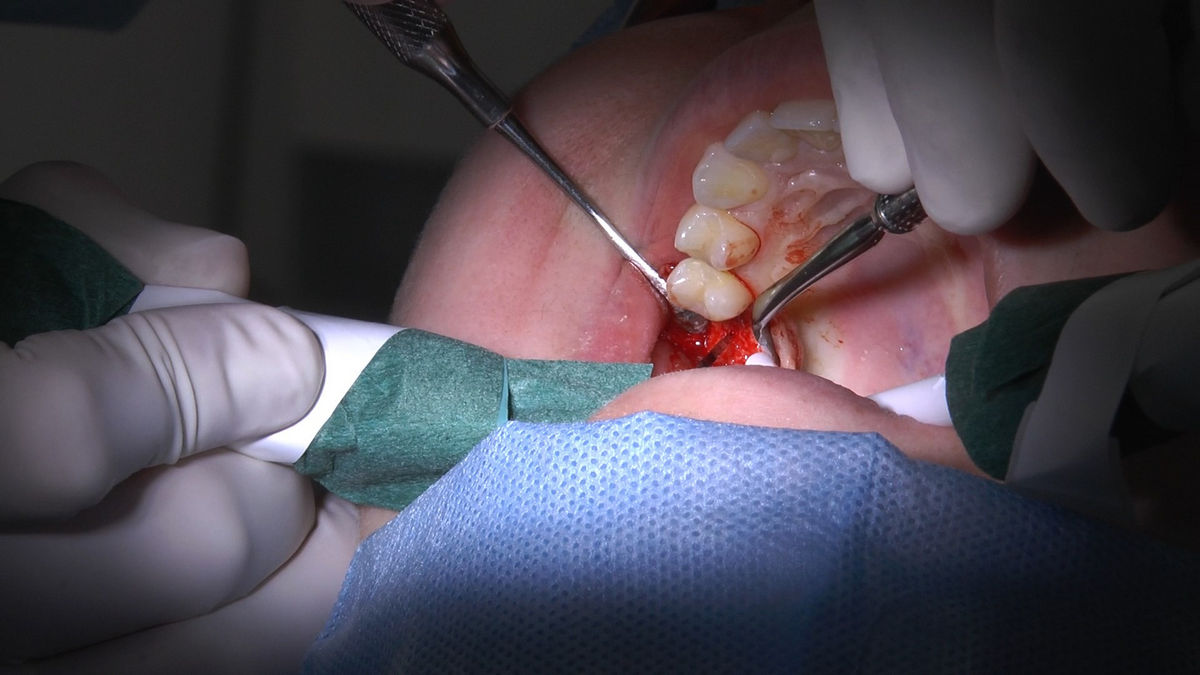

Tuż przed 100 Rocznicą Odzyskania Niepodległości, 9 i 10 listopada 2018 roku, kursanci VI Sezonu Practiculum Implantologii odbyli 7 Sesję. Dwa dni intensywnego szkolenia poświęcone zostały na zabiegi z zakresu chirurgii implantologicznej. Kursanci wykonali szereg zabiegów u Pacjentów pod kierunkiem Mentorów – dr n.med. Violetty Szycik i dr n.med. Magdaleny Kisłowskiej-Syryczyńskiej. Jak zwykle nie zaliczały się one do najłatwiejszych. W większości były przeprowadzone w arcytrudnych warunkach wynikających przede wszystkim ze stanu tkanki kostnej oraz stanu zdrowia, co wymagało precyzyjnego planowania. Z zabiegów skorzystało 17 Pacjentów, także z zastosowaniem znieczulenia ogólnego w formie sedacji dożylnej. Wszczepiono 23 implanty, wykonano zabiegi natychmiastowej implantacji po mnogich ekstrakcjach, przeprowadzono zabiegi augmentacji oraz 3 zabiegi sinus lift z zastosowaniem preparatów kościozastępczych i PRF. Wszystkie zabiegi przeprowadzane zostały zgodnie z planem i dużym stopniem samodzielności, który odpowiada zakresowi poszerzających się umiejętności szkolących się lekarzy. W panelu edukacyjnym Sukces Twojego Biznesu odbyły się pierwsze zajęcia z NLP. Kolejna 8 sesja już na początku grudnia.